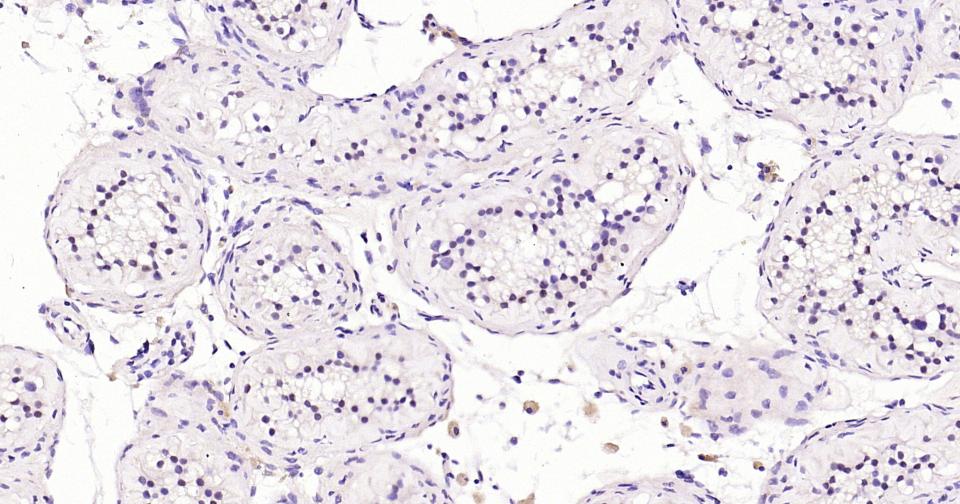

Paraformaldehyde-fixed, paraffin embedded Human Testicles; Antigen retrieval by boiling in sodium citrate buffer (pH6.0) for 15 min; Antibody incubation with WT1 Monoclonal Antibody, Unconjugated(bsm-60926R) at 1:200 overnight at 4°C, followed by conjugation to the SP Kit (Rabbit, SP-0023)and DAB (C-0010) staining.